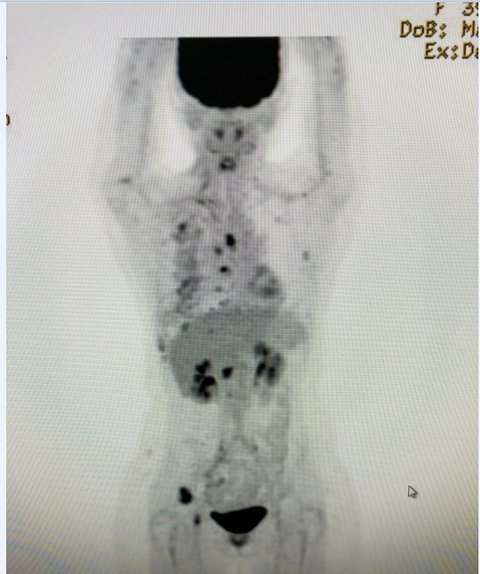

펫MRI 이라는 전신 암 진단(가장 좋은 기계으로 알고 있습니다.) 예약 했습니다.

결과가 나오기전까지..정말 머리를 복잡해지고...이 지옥같은 현실 오지 않길 열심히 기도를 하고 또 기도를 했지만...결과는 암이 뼈전이 일어났다고 하던군요........한마디 암 말기입니다..

거짓말이 생각하는 사람때문에..제 컴퓨터 모니터에서 펫 ct 사진 한장 올립니다.